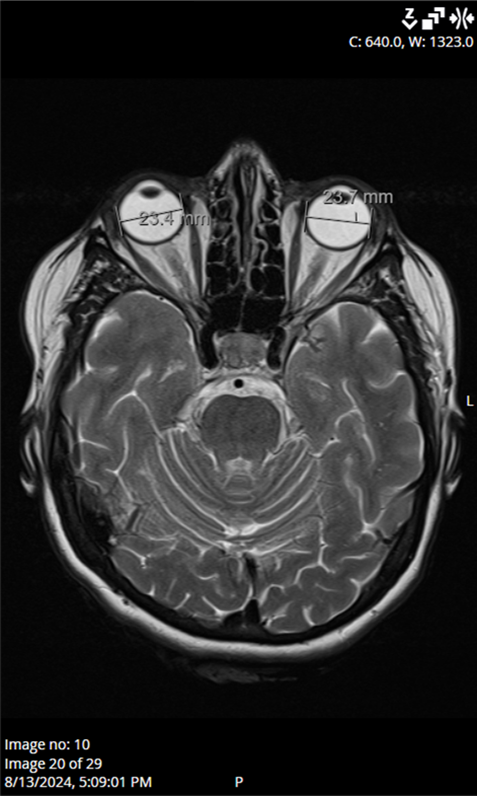

Ocular ultrasound showed a slight ONH prominence bilaterally, while computed tomography of the brain and orbits showed no pathological findings. Laboratory results, including CRP (6 mg/L), ESR (13 mm/h), platelet levels (251 × 10

9/L), blood glucose (6.3 mmol/L), and HbA1c levels (5.8%), were within acceptable ranges. Blood pressure, echocardiogram, and Doppler imaging of the carotid and vertebral arteries were unremarkable. Magnetic resonance imaging of the brain and orbits found no abnormalities to explain the optic nerve edema (

Figure 4). In addition, antibody testing for aquaporin-4 and myelin oligodendrocyte glycoprotein (MOG) was also performed during hospitalization, and the results returned negative. Serological testing for neurotropic microorganisms revealed negative results.